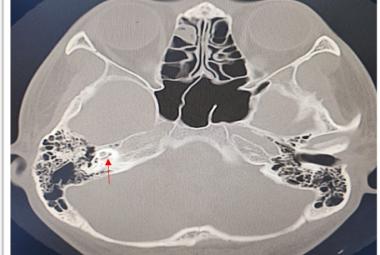

Unilateral Pulsatile Tinnitus in Young Female Adults: A Report of Two Cases